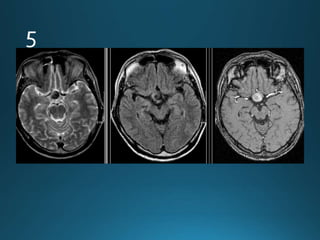

Sturge-Weber syndrome (SWS), or encephalotrigeminal angiomatosis, is a phakomatosis

characterised by facial port wine stains and pial angiomas

CT

detects subcortical calcification at an earlier age than plain film and can also demonstrate

associated parenchymal volume loss

'tram-track' subcortical calcification

MRI

T1: signal of affected region largely normal, with anatomic volume loss evident at older age

T1 C+ (Gd)

prominent leptomeningeal enhancement in affected area

T2

low signal in white matter subjacent to angioma representing

calcification later in life

abnormal deep venous drainage seen as flow voids

GE/SWI/EPI: sensitive to calcification, seen as regions of signal drop out